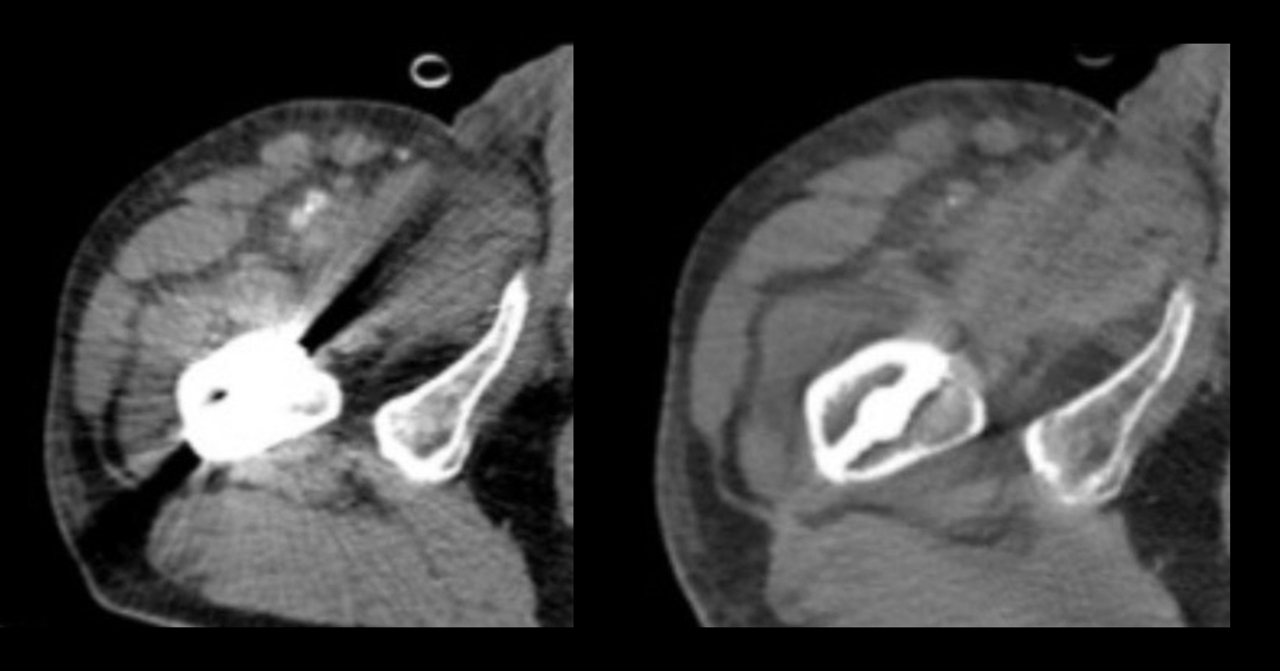

ใช้ได้กับผู้ที่มีโลหะในร่างกาย แต่ก่อนผู้ที่มีเหล็กดามกระดูกหรือข้อเทียมมักประสบปัญหาเมื่อต้องตรวจด้วย CT Scan เนื่องจากเกิดสัญญาณรบกวนในภาพ แต่เครื่องรุ่นนี้มีโปรแกรมพิเศษ (Metal Artifact Reduction) ที่ช่วยลดสัญญาณรบกวนเหล่านั้น ทำให้แพทย์มองเห็นได้ชัดเจนยิ่งขึ้น แม้ผู้ป่วยจะมีโลหะในร่างกายก็ตาม

(ซ้าย: ภาพ CT ทั่วไป / ขวา: ภาพ Spectral CT)